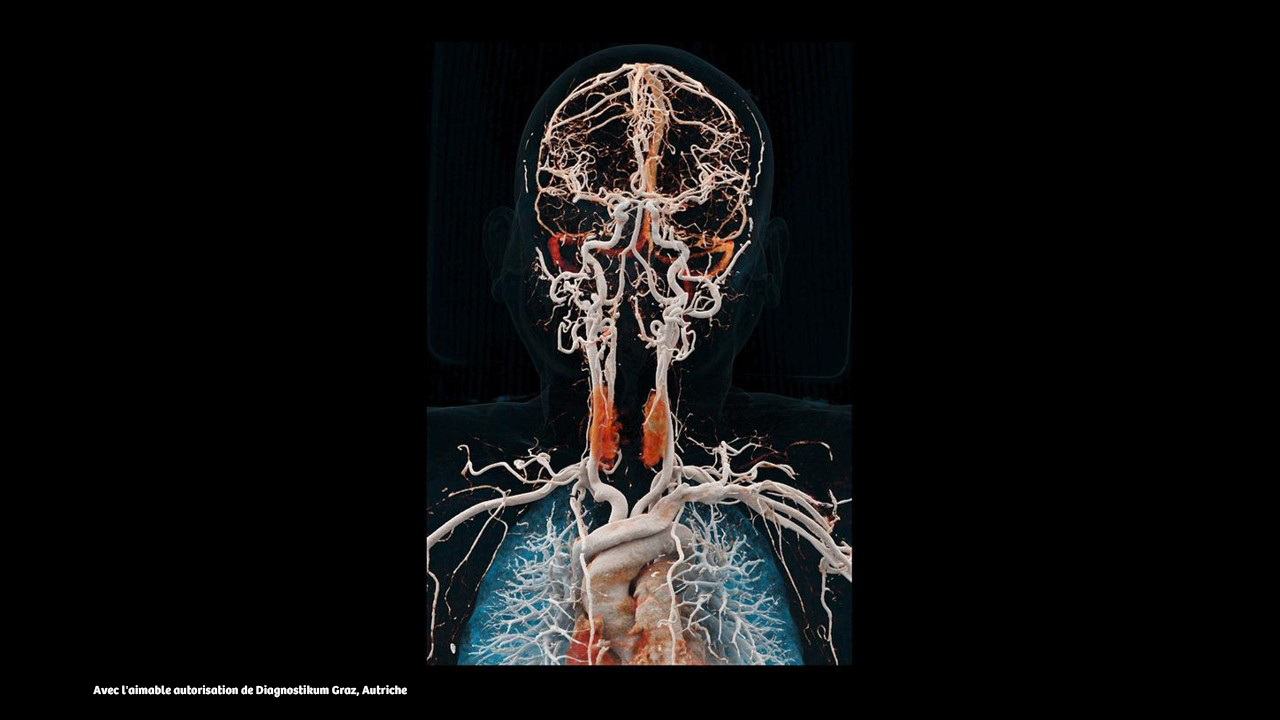

L'épaisseur de coupe unique de 0,2 mm du NAEOTOM Alpha.Prime avec Quantum HD offre une grande précision en neurologie et peut aider à optimiser les diagnostics des patients : évaluation de l'accident vasculaire cérébral, anévrisme, fistule veineuse du LCR (voir les images ci-dessus) ou oreille interne.